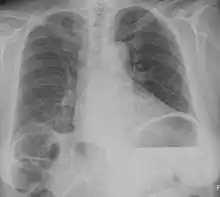

| Chest X-ray showing obvious Chilaiditi's sign, or presence of gas in the right colic angle between the liver and right hemidiaphragm. | |

Chilaiditi syndrome is a rare condition when pain occurs due to transposition of a loop of large intestine (usually transverse colon) in between the diaphragm and the liver, visible on plain abdominal X-ray or chest X-ray.[1]

Normally this causes no symptoms, and this is called Chilaiditi's sign. The sign can be permanently present, or sporadically. This anatomical variant is sometimes mistaken for the more serious condition of having air under the diaphragm (pneumoperitoneum) which is usually an indication of bowel perforation, possibly leading to surgical interventions.